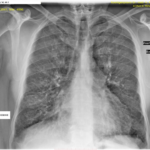

Ἡ ἀκτινογραφία θώρακος (εἰκ.2) ἔδειξε στοιχεῖα διαμέσου πνευμονικῆς ἰνώσεως (δικτυοοζώδης σκίαση) ἐντοπιζομένης κυρίως στὰ μέσα καὶ κατώτερα πνευμονικά πεδία ὑπὸ τὴν ἔννοιαν τῆς παρουσίας περιβρογχικῶν καὶ περιαγγειακῶν ἰνώσεων. Τοῦ συνέστησα περαιτέρω κλινικοεργαστηριακὸ ἔλεγχο. Μετὰ τρίμηνο ὁ ἀσθενὴς ἐπανῆλθε προσκομίζοντας τὴν τελικὴ διάγνωση τοῦ Νοσοκομείου Νοσημάτων Θώρακος << Σωτηρία>> καὶ ἡ ὁποῖα ἦταν ἰδιοπαθὴς πνευμονικὴ αἱμοσιδήρωση.Ὁ ἀσθενὴς μᾶς ἐπεσκέφθη ἔκτοτε ἄλλες δύο φορὲς τὸ 2018 (εἰκ.4) καὶ τὸ 2021 (εἰκ. 5), φαινεται δὲ ὅτι ἡ παθολογικὴ ἀκτινολογικὴ εἰκόνα ἐκ τῶν πνευμόνων δὲν ἔχει οὐσιωδῶς μεταβληθεῖ.